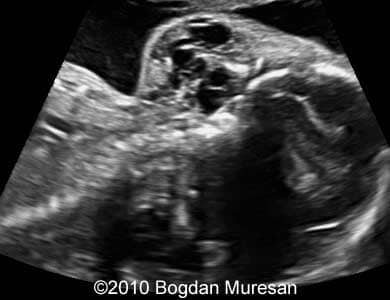

Images 1- 4: 23 weeks, parasagittal view of the cervical region, note multilocular cystic tumor located below the mandible.

Lymphangioma_Muresan_1